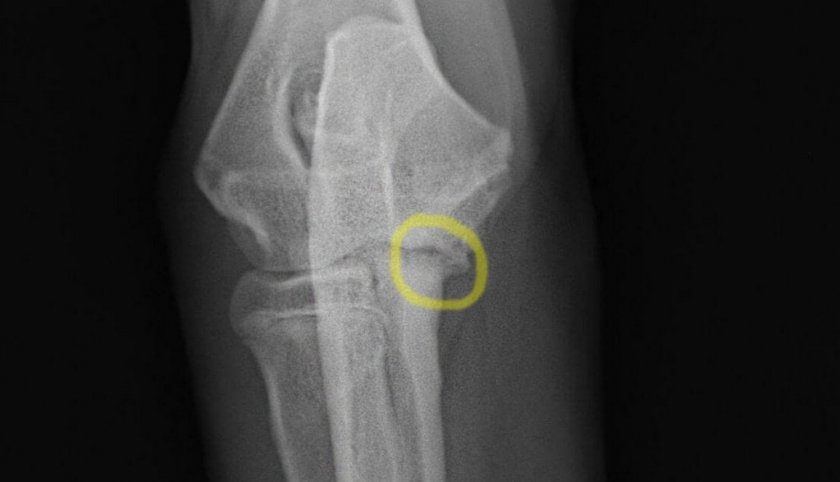

Остеохондроз относится к той небольшой категории заболеваний, для которых понятие «диагностика» предполагает выполнение вполне единственно достоверного вида обследования — рентгенографии.

В случае, если есть хоть малейшее подозрение на дегенеративные изменения хрящевой ткани или другие патологии опорно-двигательного аппарата, рентген является обязательным.

Поскольку остеохондроз, с одной стороны, далеко не всегда можно прощупать и тем более увидеть «невооружённым глазом», а, с другой стороны, патология чаще поражает один сустав, а не оба сразу, для правильной диагностики, согласно утверждённой и общепринятой методики, необходимо получить качественные и подробные снимки двух зеркальных суставов и затем сравнить их между собой. Каждая область просвечивается в двух перпендикулярных проекциях — обычно для этого выполняются фронтальный и боковой снимки.

Чтобы получить полное представление о состоянии костей и хряща, сустав необходимо привести в определённое положение, причём, как правило, оно является именно тем, в котором собака испытывает максимальную боль. При этом очень важно, чтобы животное во время процедуры находилось в абсолютно неподвижном состоянии, иначе снимки получатся нечёткими. Именно поэтому не стоит удивляться тому, что рентгенография у собак проводится под наркозом. Большинство современных клиник используют с этой целью седацию, т.е. наиболее мягкую и безопасную форму общей анестезии, но даже в этом случае определённый риск для жизни и здоровья питомца сохраняется, а потому хозяину стоит уточнить у доктора, какой именно препарат он будет применять и имеются ли в учреждении все необходимые средства для обеспечения безопасной реверсии животного (выведения из наркоза).